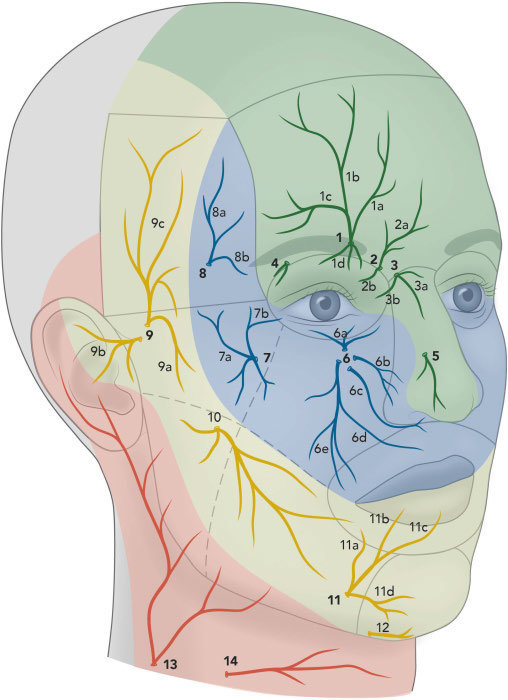

Don't hit super hard , check a nerve map to avoid hitting it , and be careful,im also using a hammer but im not hitting that hard. slow intensity btw like ive seen people do it very hard like until it bruises to a very bad state but they never had nerve damge lmao how did he get it like did was he hitting like super crazy hard?

do u check the nerve map and try not to hit a nerve?Don't hit super hard , check a nerve map to avoid hitting it , and be careful,

You can ,do u check the nerve map and try not to hit a nerve?

How am i suppose to not hit a nerve on zygos bro

View attachment 4458013

There is a small check you can do, hit the zygo one or two times

If you felt some twitchy pain , that's a nerve if you just hit a bone ; it is safe

Just don't fucking hit super hard